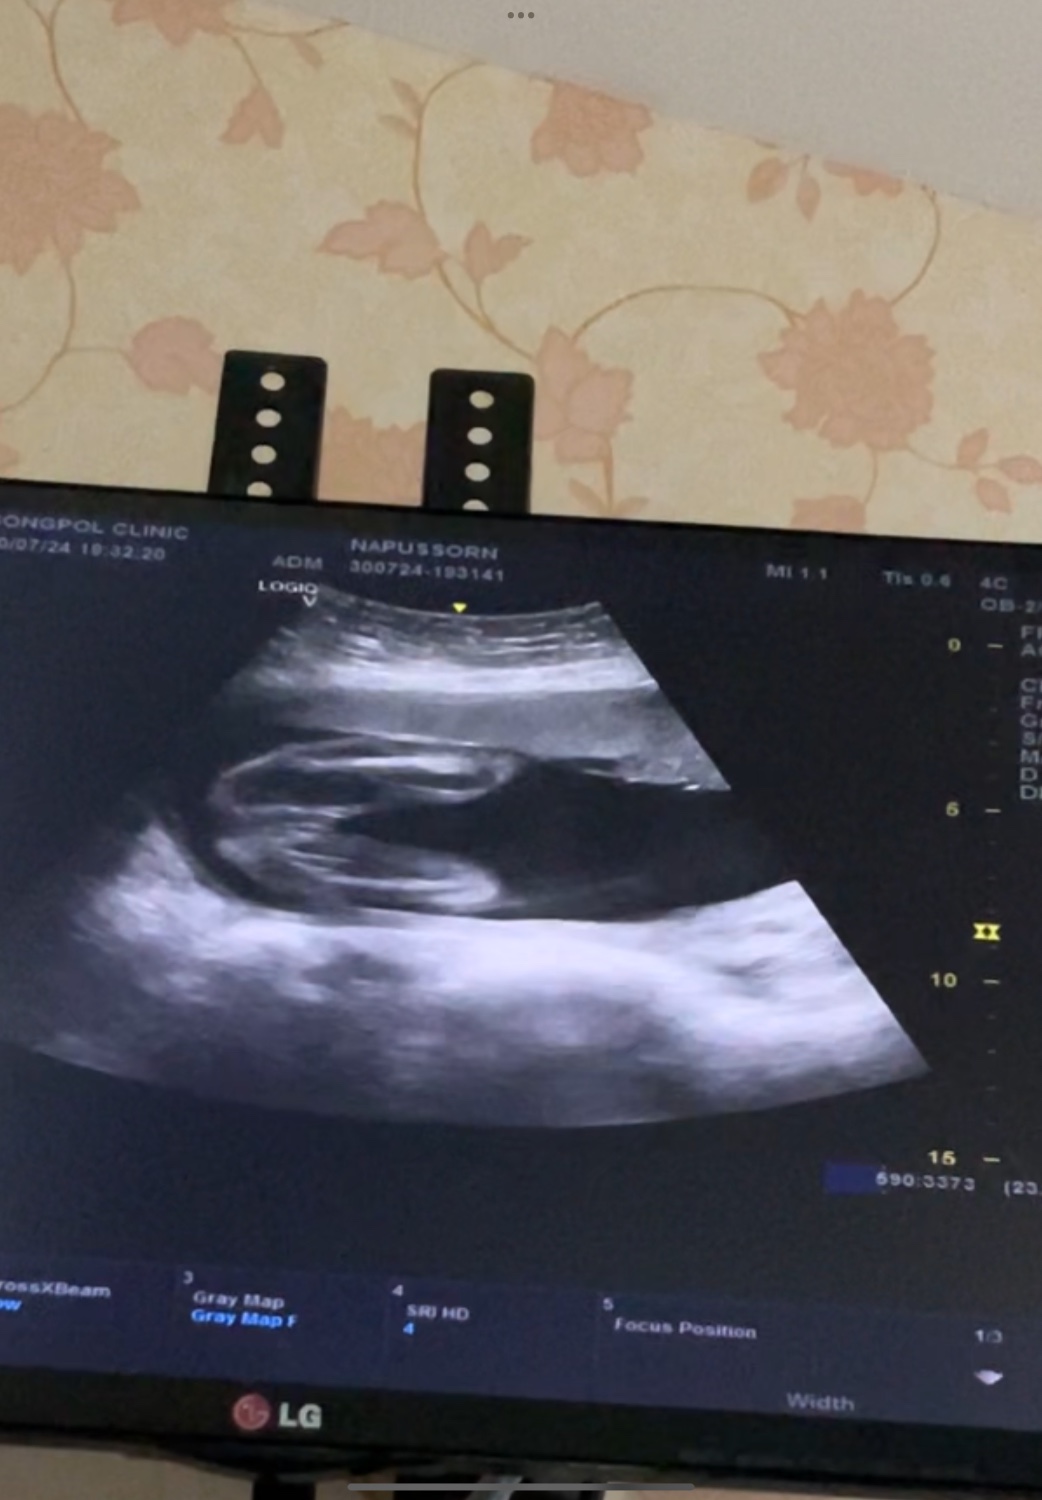

ช่วยดูผลอัลตราซาวหน่อยค่ะ

เพื่อนๆพี่ๆน้องๆช่วยดูผลอัลตราซาวหน่อยค่ะพอดีไปหาหมอมาหมอบอกว่าน้องเป็นเพศ ญ. แต่แม่ไม่มั่นใจเลยอยากให้ทุกคนช่วยดู